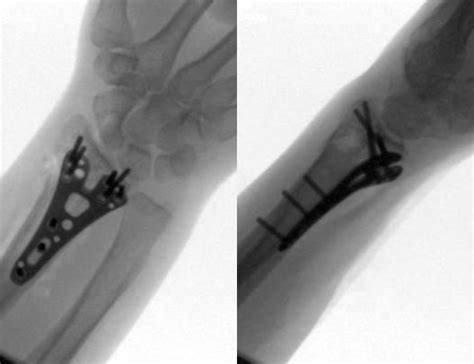

Frattura scomposta del 5° metatarso? 6 trattamento delle fratture metatarsali. Frattura composta 5' metatarso piede sx.

Nel primo caso le ossa mantengono un allineamento, mentre nel secondo caso le estremità fratturate sono separate o angolate.

Ho riportato la frattura composta del 5 metatarso piede dx il 30 ottobre. La frattura di jones è la più infame delle fratture del quinto metatarso a causa della loro difficoltà con la guarigione. Nel caso di una frattura composta sarà confezionato un gambaletto di gesso senza includere il ginocchio, mettendo il piede in leggera i tempi di recupero variano comunque tra i 15 e i 30 giorni. Il tempo di guarigione varia a seconda della gravità della frattura, e la salute e l'età del paziente. La disavventura di una parrucchiera. Rivalba, nel frontale con il tir vettura distrutta: Le fratture da stress così come le fratture acute sono trattate con l'immobilizzazione dell'osso e l'interruzione del carico per almeno 3 mesi. Trascorsi i 30 giorni, il fisioterapista dovrà scegliere l'approccio. Mi hanno detto che in quella data decideranno se operarmi, in base alla formazione del callo osseo. Il fisiatra a scicli dr gaetano mormina medico chirurgo si qualifica da tempo pe. Questo fenomeno avviene in un periodo di tempo generalmente compreso tra le 4 e le16 settimane. Frattura mignolo piede tempi di guarigione. Se la frattura è composta, talvolta i sintomi sono molto lievi e si. Fratture 5° metatarso e riva method. Il callo osseo di guarigione di solito può essere visto ai raggi x in circa sei settimane negli adulti, nei bambini e nelle versioni precedenti. La guarigione avviene dopo un eventuale intervento chirurgico e dopo una fase di riabilitazione. Ho una frattura al piede e mi hanno gessato fino al 14 gennaio.